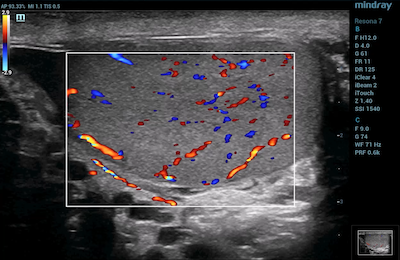

- Breast Imaging – CDI helps to determine the absence of flow in breast lesions. This is useful in distinguishing breast cancer from benign pathological conditions.

Color Doppler Ultra Micro Angiography of Breast Malginancy

Color Doppler Imaging of Breast Fibroadenoma